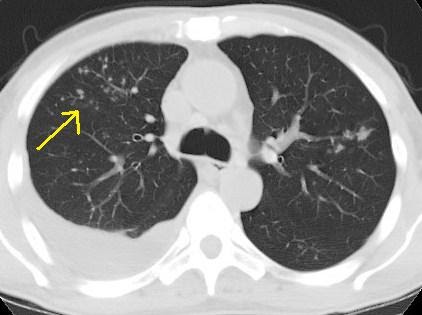

Multiple diffuse patchy opacities are seen in lung fibrosis, Pneumocystitis carnii pneumonia, allergic pneumonitis, and in occupational lung diseases (pneumoconiosis). Diffuse alveolar patchy opacities are seen in lung edema in heart failure, alveolar haemorrhage, acute respiratory distress syndrome and. Linear opacity in lung Linear opacities in the lung base are noted compatible with subsegmental atelectasis? Meaning (asthma, cough, flem, no fever, seen specialist. Pulmonary opacity is a nonspecific term describing an area of increased pulmonary attenuation caused by an intraparenchymal process. Dec 18, 2012Key findings in hydrostatic pulmonary oedema are cardiomegaly, dilatation of pulmonary veins, peribronchovascular thickening and lower lobe predominance. However, pulmonary oedema may occur in the absence of an enlarged heart silhouette in cases of mitral reflux, left atrial enlargement and elevated pulmonary artery pressure. Consolidation may be patchy in distribution and involve only certain lobules of the lung although it can be widespread and affect entire lobes of the lung. In pulmonar embolism it is not common to see consolidation. The consolidation is a result of lunginfarction and bleeding into the alveoli. In this case a lung cyst has formed in the infarcted area. Here we see an old chest film, which is normal. The pulmonary embolus has caused a triangular density on the chest film (arrow). Consolidation may be patchy, lobar, multilobar, or round and may opacities on the chest Xray may produce the appearance of multiple small nodules. Pulmonary opacification represents the result of a decrease in the ratio of gas to soft tissue (blood, lung parenchyma and stroma) in the lung. Oct 20, 2006What do you mean streak opacity in the lungs? Are you sure you want to delete this answer? Type Of Opacity Common causes (some of which are not routinely imaged by HRCT) include pulmonary edema; ARDS; viral, mycoplasmal, and pneumocystis pneumonias; hypersensitivity pneumonia; pulmonary hemorrhage; and other diffuse interstitial lung diseases. Many airspace filling processes can also result in consolidation in advanced disease. There is still patchy opacity of the lung fields. She slowly improved after about a week of intensive care including inhaled nitric oxide. Interstitial lung disease (ILD) is a characterized by multiple small nodular opacities on the chest x and organizing pneumonia is seen with patchy. Lung Parenchymal Disease: nodular opacities are the size of pulmonary often used to better show lung tissue disease. Differential diagnosis of the causes of pulmonary opacities on chest xray Apr 04, 2006Best Answer: Opacity means an area in the lung that shows up white on an xrayso an area that light can't pass through. Patchy opacity in lung I have patchy opacity in both lungs hypertrophied turbinates. Can it be treated non surgically? Bibasilar opacities, atelectasis versus early consolidation. Focal nodular opacity at the left lung base, possibly due to atelectasis or confluence of vessels, PFTAbnormal FVC; 2. There is mild restrictive ventilatory defect with normal DLCO. Chest Radiology Pathology Pneumonia. The xray findings of pneumonia are airspace opacity, mechanical vent pts, high mortality rate, patchy opacities. The three common patterns seen are patchy or airspace opacities; linear opacities; and nodular or dot opacities. Airspace or patchy opacities may represent consolidation, atelectasis or mucoid impaction. Consolidation indicates solid or liquid occupying the normally gaseous areas in the lungs and may be due to accumulation of fluid, pus, blood, cells, gastric contents, protein or even fat in the lungs. Just had a cat scan done with the following results A new. 4cm nodule in the left lower lobe is noted. New focal patchy and ground glass opacities in the right lung. Air space opacification is a descriptive term that refers to filling of the pulmonary tree with material that attenuates xrays more than the surrounding lung parenchyma. Atelectasis Comprehensive overview covers symptoms and causes of a partly or completely collapsed lung.